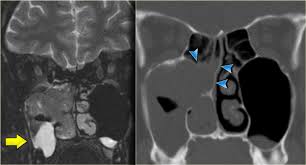

If a patient has abdominal pain or appears to have a swollen abdomen, the health care professional may have X-rays taken to show intestinal obstruction or perforation. X-rays can also be taken after the patient drinks X-ray dye to show the GI tract, which can be followed up with an internal view of the colon through colonoscopy, if problems are noted.